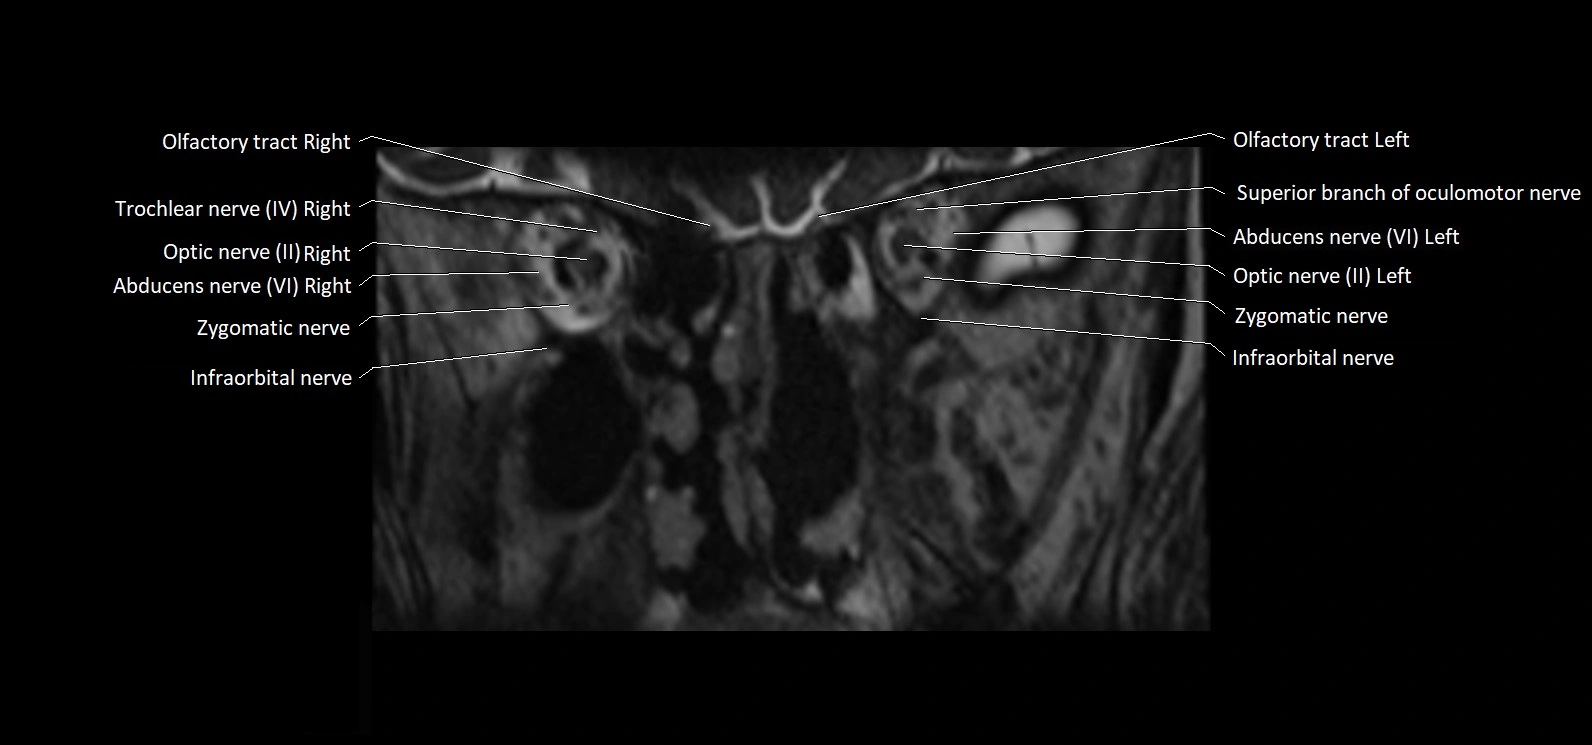

MRI Appearance

• The abducens nerve is a small, thin, linear structure

• Best visualized on high-resolution T2-weighted 3D MRI sequences (e.g., FIESTA or CISS)

• Seen as a hypointense (dark) line running from the brainstem at the pontomedullary junction, traversing the prepontine cistern, and entering Dorello’s canal under the petrosphenoidal ligament, then into the cavernous sinus, and finally the orbit

• May be challenging to visualize in standard MRI due to its small size

• Pathology may be inferred by absence, displacement, or enhancement of the nerve

MRI images

image